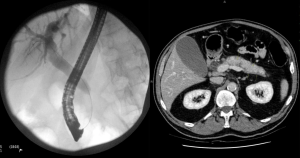

A 62-year-old man presents with painless jaundice. ERCP and CT images are shown below. What is your diagnosis?